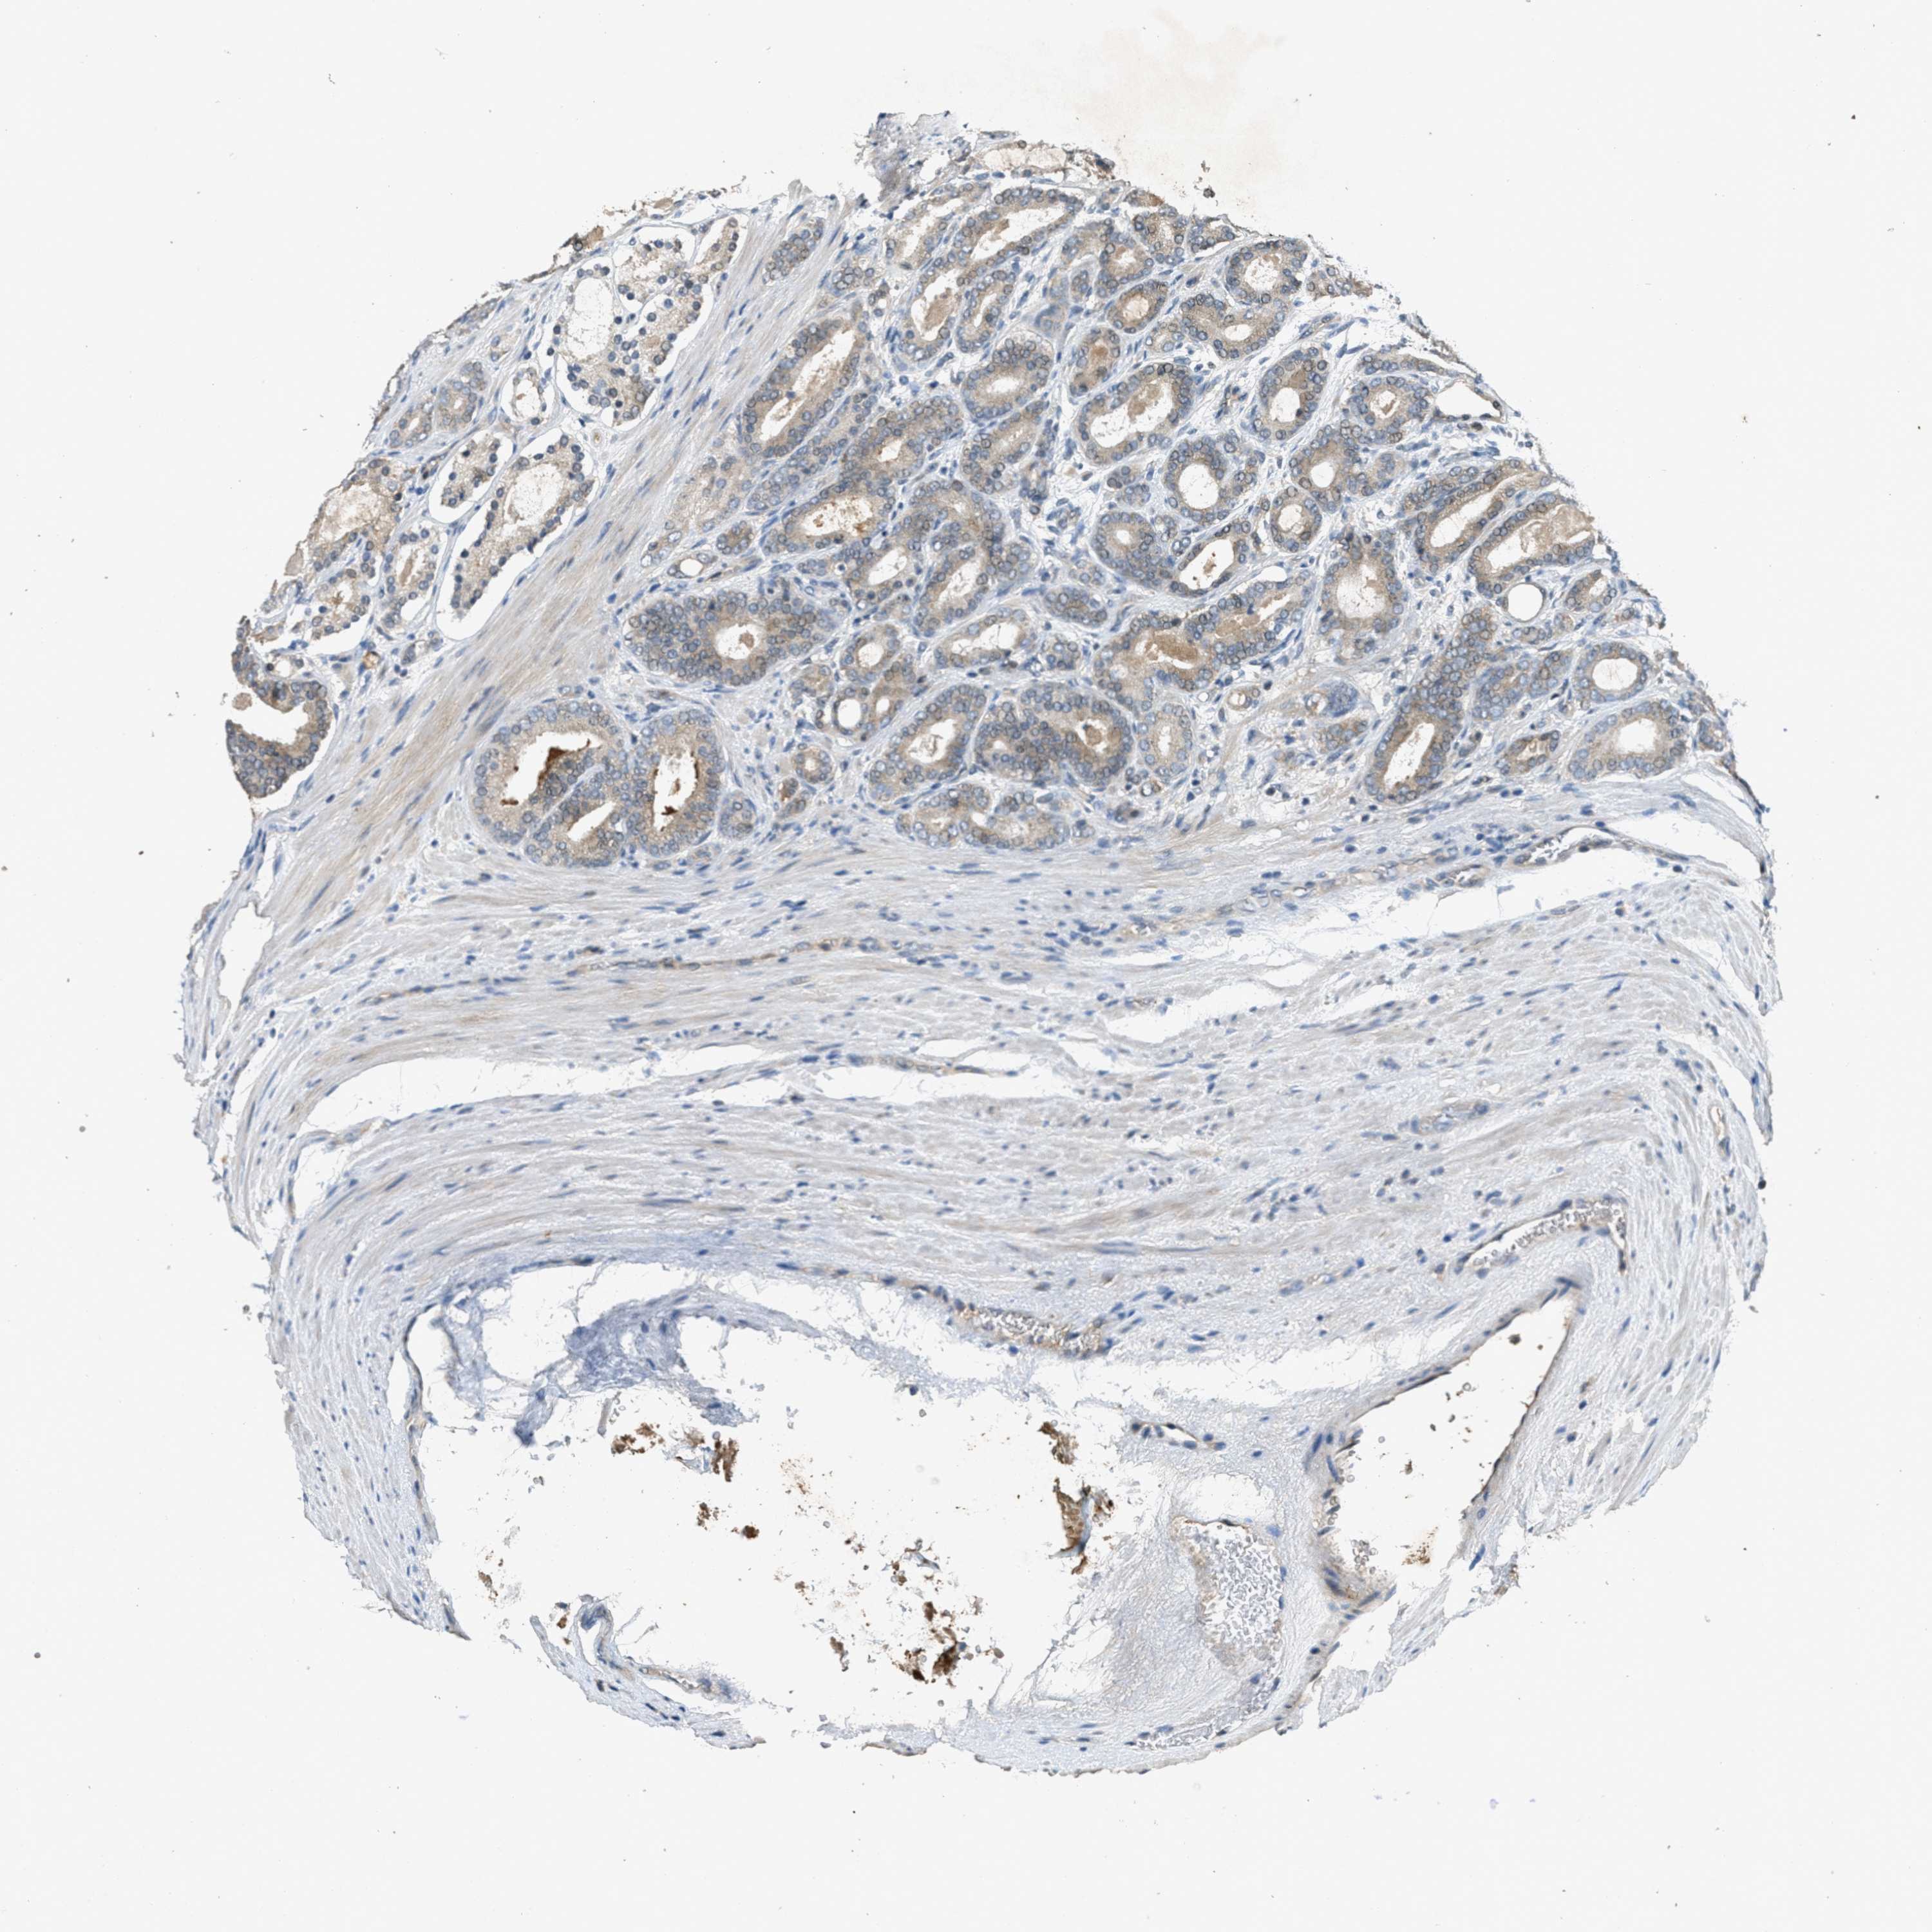

PROSTATE CANCER - Protein expressioni

A mouse-over function shows sample information and annotation data. Click on an image to view it in a full screen mode. Samples can be filtered based on level of antibody staining by selecting one or several of the following categories: high, medium, low and not detected. The assay and annotation is described here.

Note that samples used for immunohistochemistry by the Human Protein Atlas do not correspond to samples in the TCGA dataset.

Antibody stainingi

Antibody staining in the annotated cell types in the current human tissue is reported as not detected, low, medium, or high, based on conventional immunohistochemistry profiling in selected tissues. This score is based on the combination of the staining intensity and fraction of stained cells.

Each image is clickable and will lead to virtual microscopy that enables deeper exploration of all samples and also displays staining intensity scores, fraction scores and subcellular localization as well as patient and tissue information for each sample.

Antibody CAB017566

Staining

High

Medium

Low

Not detected

Intensity

Strong

Moderate

Weak

Negative

Quantity

>75%

75%-25%

<25%

None

Location

Nuclear

Cytoplasmic/membranous

Cytoplasmic/membranous,nuclear

Adenocarcinoma, High grade

Adenocarcinoma, Low grade